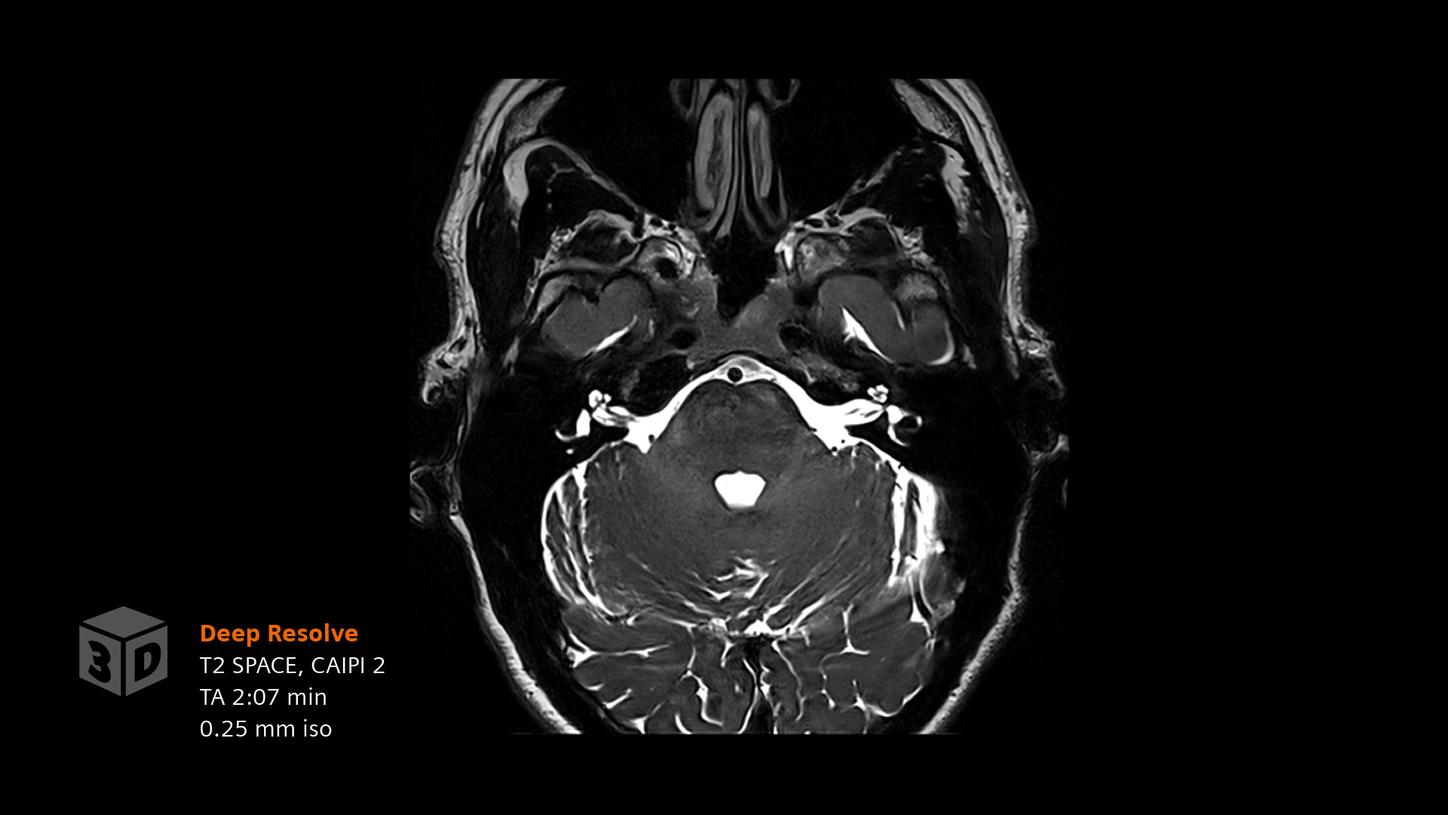

Siemens Healthineers. (n.d.). Deep Resolve - AI-powered image reconstruction. Retrieved from https://www.siemens-healthineers.com/magnetic-resonance-imaging/technologies-and-innovations/deep-resolve

Deep Resolve 3D is currently under development and not commercially available. Its future availability cannot be guaranteed.